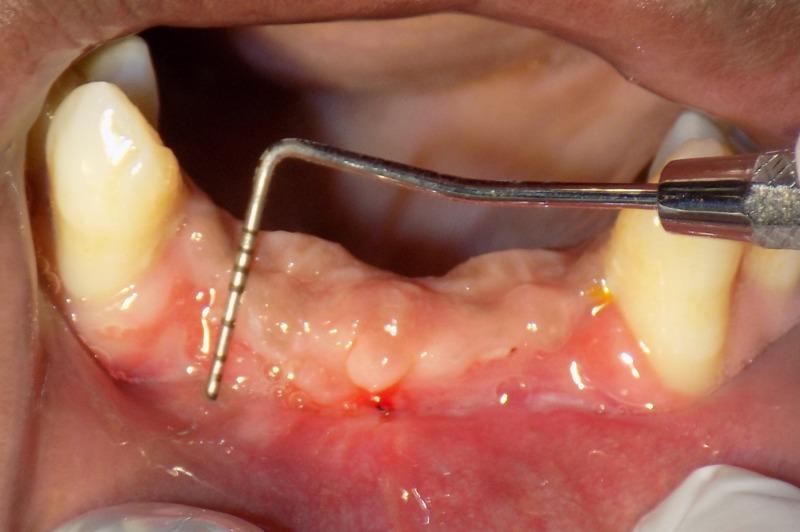

固定修复干预中附着龈减少的浅前庭管理

Management of Shallow Vestibule with Reduced Attached Gingiva in Fixed Prosthetic Intervention.

Shallow vestibule has long been considered a deterring factor in the use of removable dental prosthetics. The need for management in fixed prosthetic replacement is not widely discussed. Adequate attached gingiva is essential for continued proper oral hygiene. Muscular and fibrous traction leads to gingival recession, which can cause marginal leakage in a fixed prosthetic restoration. In the long-term, this causes the suprastructure to fail and, ultimately, the restoration also fails. Therefore, shallow vestibule with reduced attached gingiva should be identified in the diagnostic stage and should be effectively managed prior to restoration of lost tooth structure. This case report discusses the management of a shallow vestibule in a LeFort I fracture with emphasis on a fixed prosthetic replacement.

摘要

浅前庭长期以来一直被认为是使用可摘义齿的一个阻碍因素。固定义齿修复中管理需求的讨论并不广泛。足够的附着龈对于持续保持良好的口腔卫生至关重要。肌肉和纤维的牵拉会导致牙龈退缩,这可能在固定义齿修复中引起边缘渗漏。从长期来看,这会导致上部结构失败,最终修复体也会失败。因此,在诊断阶段就应识别出伴有附着龈减少的浅前庭,并在修复缺失牙体结构之前进行有效管理。本病例报告讨论了LeFort I型骨折中浅前庭的管理,重点是固定义齿修复。